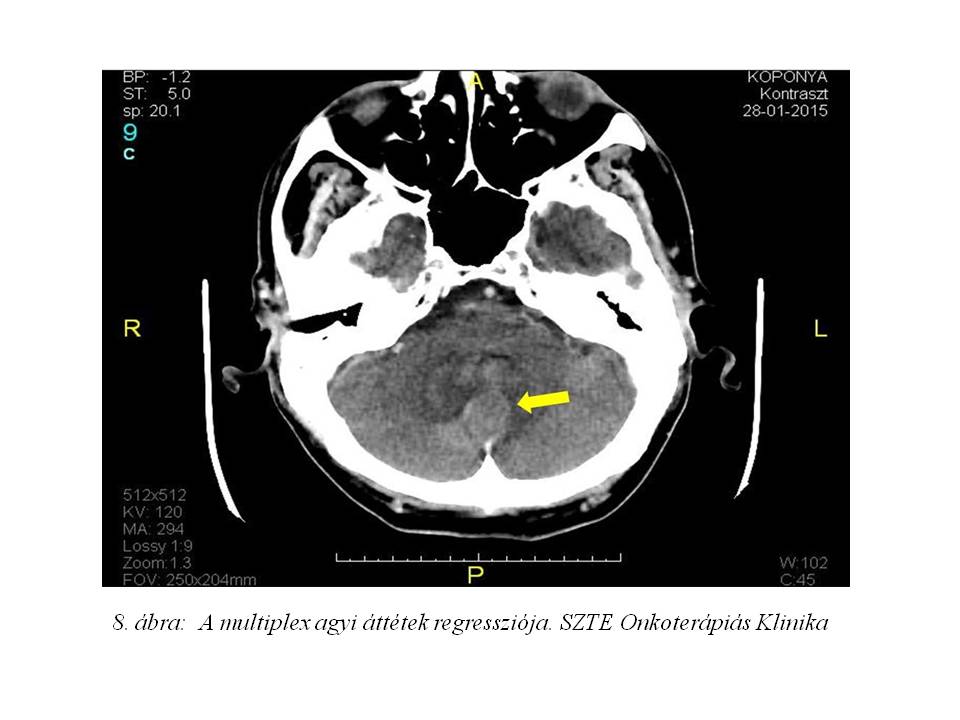

A kezelés megkezdése előtt kontroll koponya CT vizsgálat készült, mely a korábbi multiplex gócoknál regressziót véleményezett (7. ábra, 8. ábra).